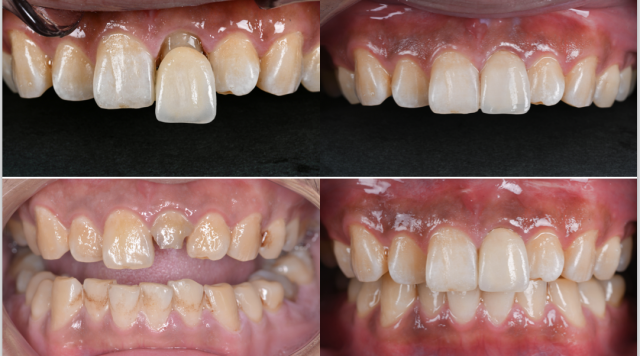

术前口内照片 A.术前唇面照;B.术前黑背板照;C.术前舌侧照;D.术前牙齿宽度测量;E.牙周基础治疗后的比色照;F.偏振光照看牙齿纹理

A.树脂核堆塑;B.牙体预备;C.根尖保留4mm根充物植入纤维桩的术后影像;D.两中切牙近远中比例检测;E.11去龋;F.11树脂充填,11、22邻面去釉抛光

处理:口内试戴全瓷冠,检查就位情况、冠边缘密合无悬突、邻接关系紧密、外形及颜色患者满意、无咬合高点及咬合干扰,粘固修复体。